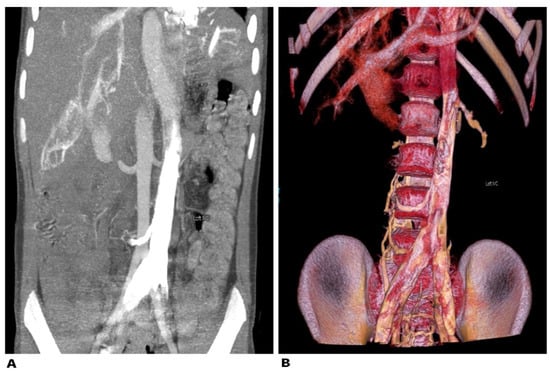

- Duan, H.; Liu, P.; Chen, C.; Chen, L.; Li, P.; Li, W.; Gong, S.; Xv, Y.; Chen, R.; Tang, L. Reconstruction of three-dimensional vascular models for lymphadenectomy before surgery. Minim. Invasive Ther. Allied Technol. 2020, 29, 42–48. [Google Scholar] [CrossRef]